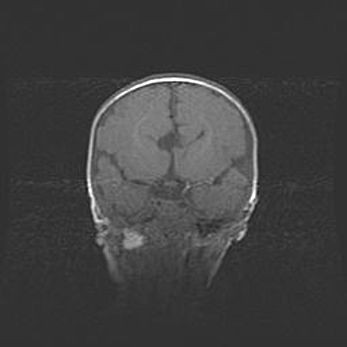

Множественные кисты обоих полушарий головного мозга, наибольшая из них в правой затылочной области. Ассиметричная атрофическая гидроцефалия.

Возраст: 7 месяцев

Вес: 5660 г

Пол: мужской

Окружность головы: 41,5 см

Срок гестации: 28-29 недель

Кисты головного мозга развиваются в результате многоочаговых некрозов вещества мозга и возникают вследствие перенесенной перинатальной инфекции, менингитов, энцефалитов, асфиксии, родовой травмы, расстройств мозгового кровообращения различного генеза. Образованию кист в веществе головного мозга плодов и новорожденных способствуют такие факторы, как высокое содержание в нем воды, недостаточная (или отсутствие) миелинизация и слабая астроглиальная реакция на повреждение.

Кисты могут сочетаться с гидроцефалией и другими поражениями головного мозга.